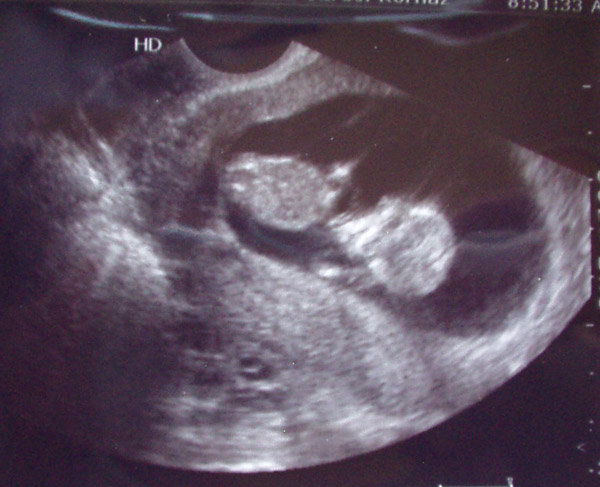

Kazincbarcikára elmentünk 11+3 hetesen uh-ra. Ez most volt reggel. Egy ismerős ott szonográfus. megcsinálta a vizsgálatot. Szerencsére rendben talált minket.

CRL: 47 mm

BDP: 17 mm

NT: 2 mm

És itt van 2 kép a kicsiről. Mindkettőn alul van a feje, és elölről lehet látni.